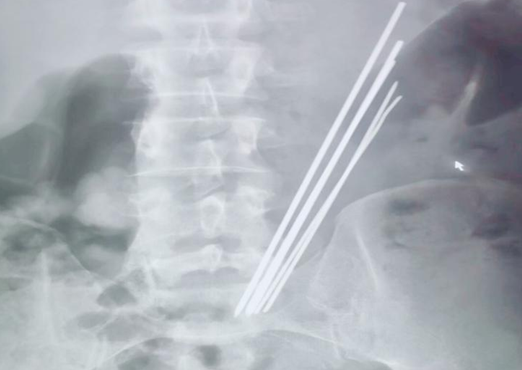

2019年10月30日,延安大学咸阳医院内镜中心一如既往,仍是一番忙碌景象。电话响起,我院普外科二病区来电,科室就诊了一位特殊患者,又一例消化道异物,与此前不同的是,这位病患的异物已吞入达3年之久,间断腹痛,未予重视及治疗,近来因脐周疼痛逐日加重,就诊于多家医院,无一例外,均建议手术,患者及家属疲于奔波,最终无奈接受,遂来我院要求行手术治疗。主管医师接诊后积极询问病史,完善相关检查,令人讶异的是,3年时间异物依旧潴留于胃腔之中,腹平片提示为多个长条状金属异物,棘手之处在于患者拒绝提供关于异物的详细信息。听闻我科上次胃内异物取出报道,主管医生抱着试试看的态度打通了内镜室的电话。

李恒副主任医师详细了解上述情况后,立即与内镜中心麻醉师张玉河医生沟通,暂时无法确认异物是否嵌顿入胃壁,以及其嵌入深度,普通胃镜的刺激极有可能加剧患者痛苦,为异物取出造成阻碍,无痛胃镜相对而言,患者痛苦较小,避免了配合度不高等情况,但与此同时,因异物存留于胃腔内时间较长,考虑金属质地,且数量较多,操作过程中必然会面临很多棘手问题,并发呼吸困难、大出血的风险。消化内科一病区李主任和麻醉医师张玉河认真翻阅患者相关信息,制定出严谨、详尽的治疗方案。征得患者及家属同意后,又一场攻坚战展开了......进镜至胃腔,可见5个长条形金属异物滞留,表面光滑,粘液附着,抓取难度非常之大,需在胃腔内不断调整方向,确保异物以竖直状态随胃镜缓慢退出,避免异物通过食管及口腔时造成的二次损伤,经过反复不懈努力,最终异物全部安全取出,长条状金属异物最长达16cm左右。患者家属难掩兴奋之情,不停的念叨着“谢谢,谢谢”,内镜下的异物取出让他们的亲人免受手术之苦,同时也减轻了经济负担。